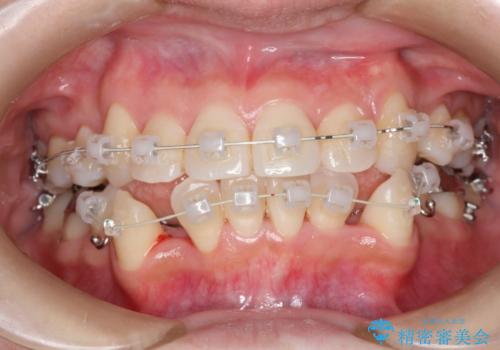

コンプレックスだった前歯のガタガタがここまで綺麗になるなんて!!

- 審美装置(ブラケット:白/ワイヤー:白)

初診時の歯並びの状態としては、上下に強いガタガタがある状態であり、それが原因で口腔内の清掃状態も極めて悪い状況でした。

スペースの不足量が著しく、上下左右の抜歯を伴うワイヤー矯正にて治療を行いました。

抜歯によるスペースを利用し、強いがたつきの改善を行いました。